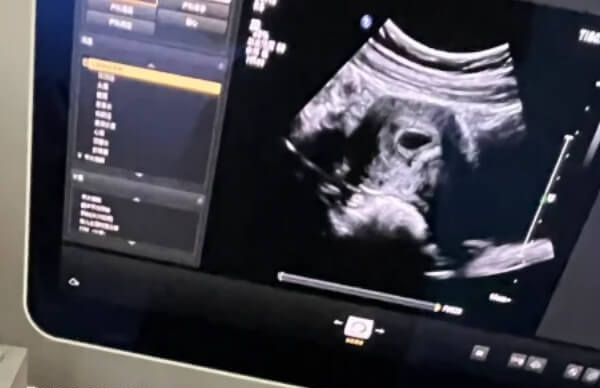

一般来说,试管促排卵出现空卵泡的时候,可能是女性卵巢功能出现异常所导致,或者是卵泡虽然在生长,但卵子早期发生闭锁现象,出现空卵泡情况。而这都不太会引起空囊的情况,对此可见,促排对空囊的影响不大。

促排可能会使一些原本质量不佳、染色体存在异常的卵子被排出并受精。这些异常的胚胎在发育过程中容易出现空囊现象,因为染色体异常会影响胚胎的正常发育,导致胚胎无法正常形成卵黄囊、胎芽等结构。